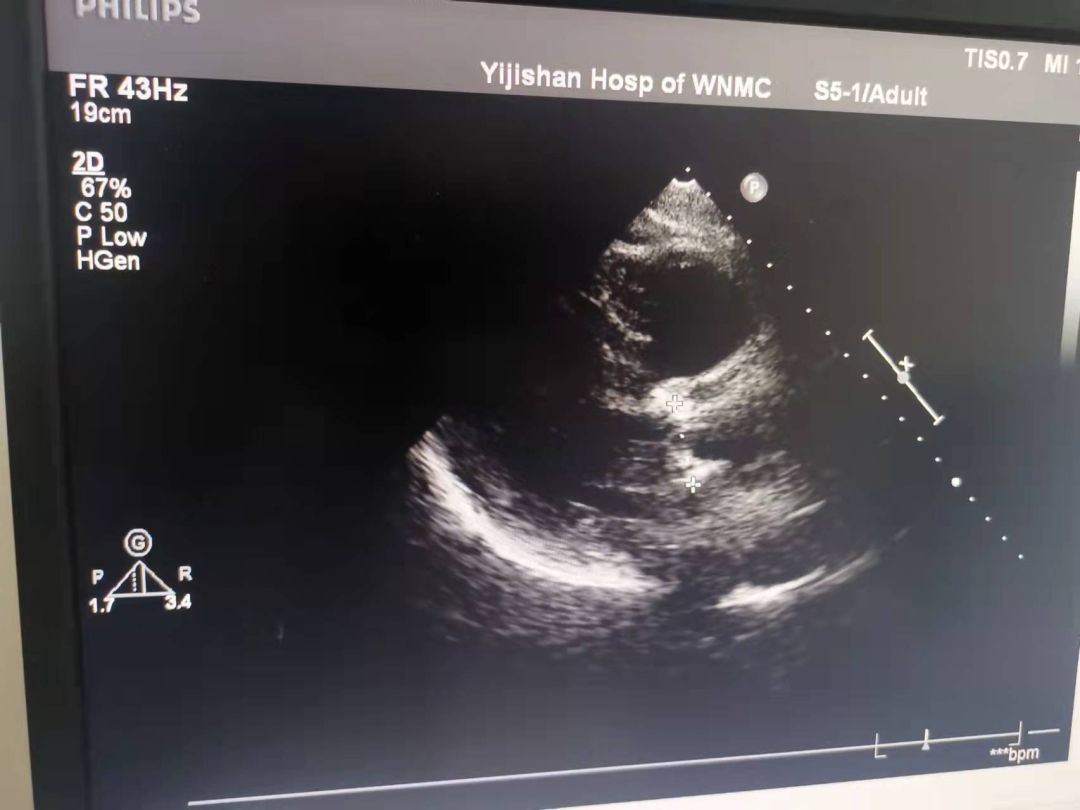

术后经心尖超声

经猪尾导管复查造影:瓣膜支架系统膨胀良好,未见瓣周漏,冠脉显影正常,食道超声提示瓣膜工作正常,压差解除,无瓣周漏。